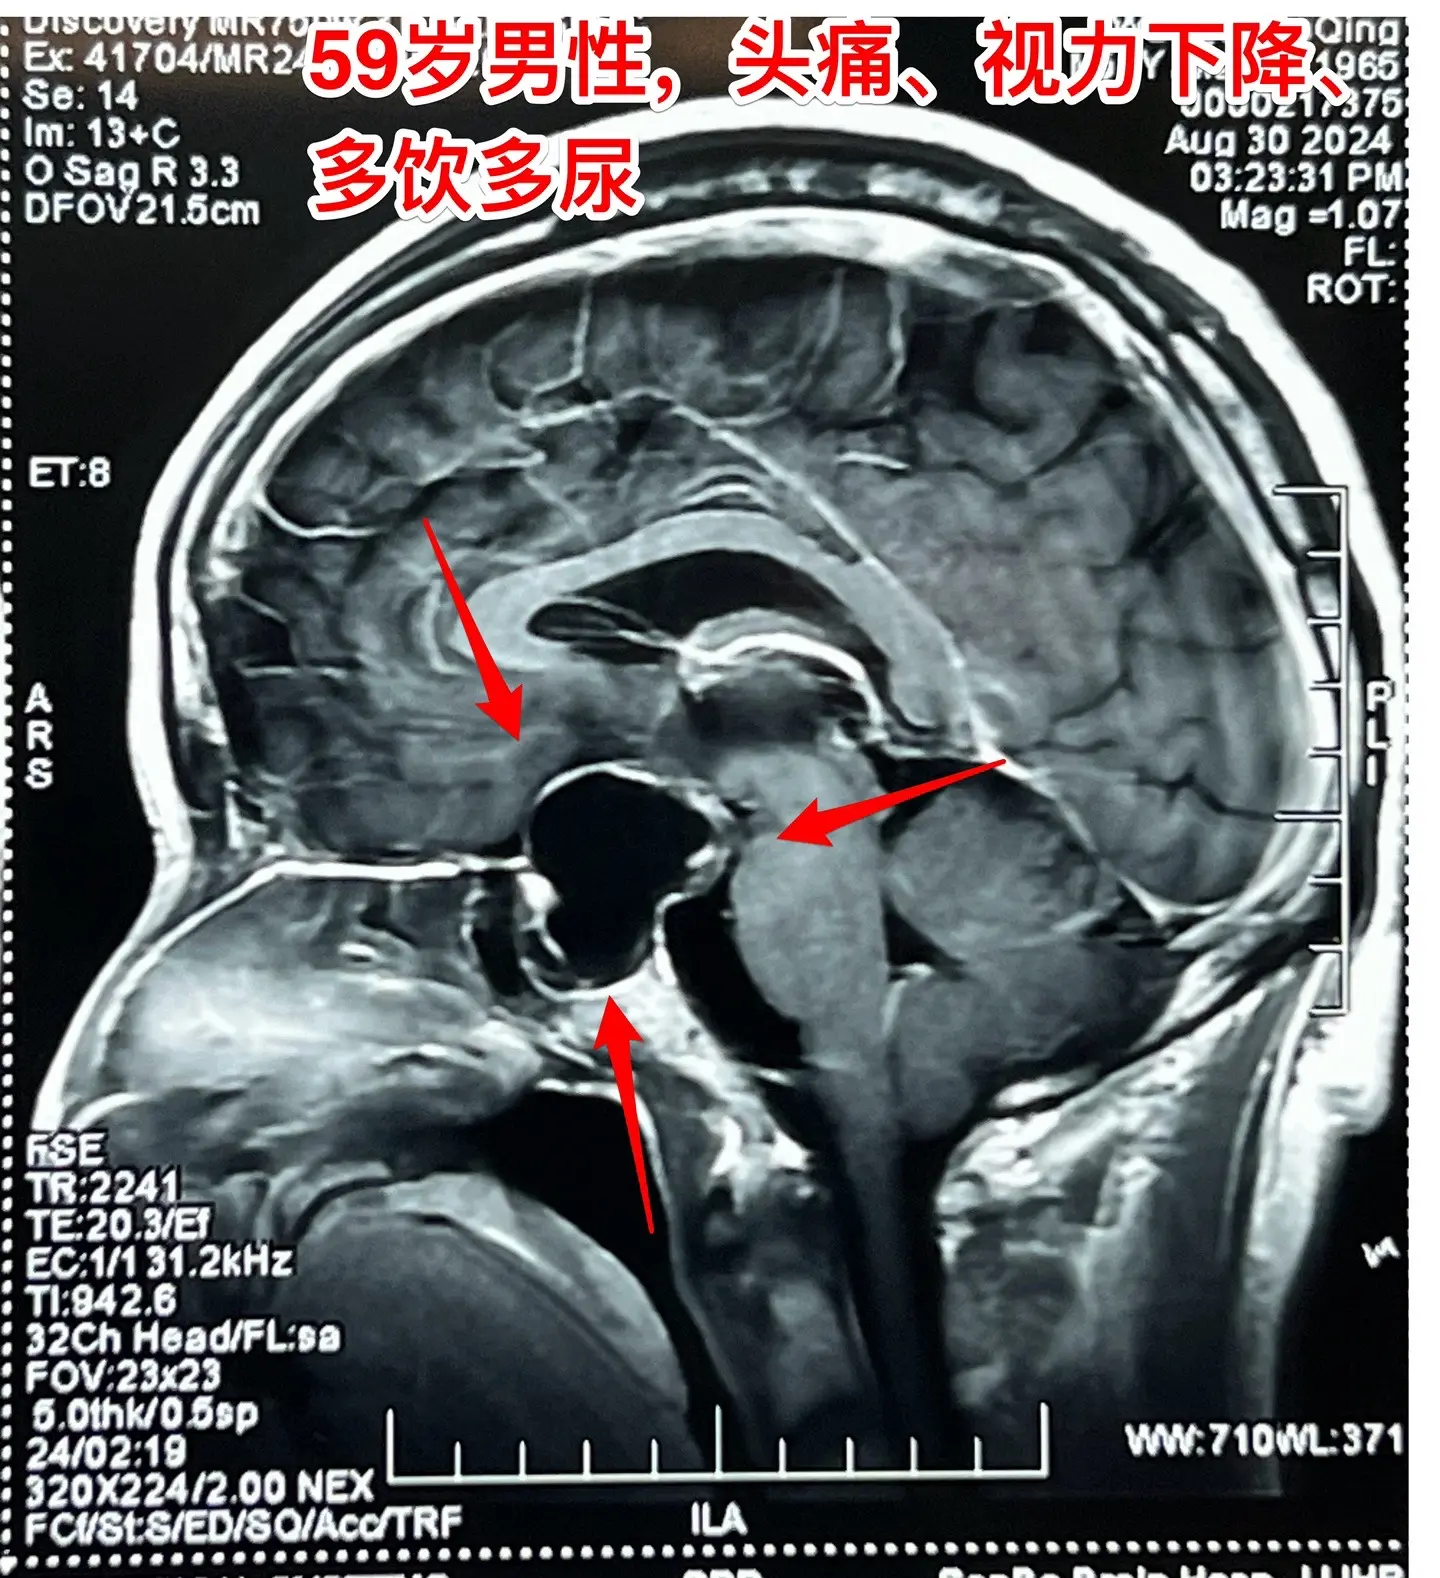

头痛、视力下降、多饮多尿、体重下降。59岁洛阳市男性,近三年感头痛,近一年半感觉视力下降,以为是老花眼,未就医。近9个月多饮多尿,夜间睡眠很差,白天精神很差。近半年体重下降25斤。 2024.8.23到医院就诊,作头部磁共振发现颅咽管瘤。2024.9.5在我科行开颅手术切除颅咽管瘤。手术中发现肿瘤是囊性的,内壁有瘤结节,没有钙化,所以是乳头型颅咽管瘤,肿瘤得到完全切除。手术后双眼视力显著改善。(今年的第133例颅咽管瘤)